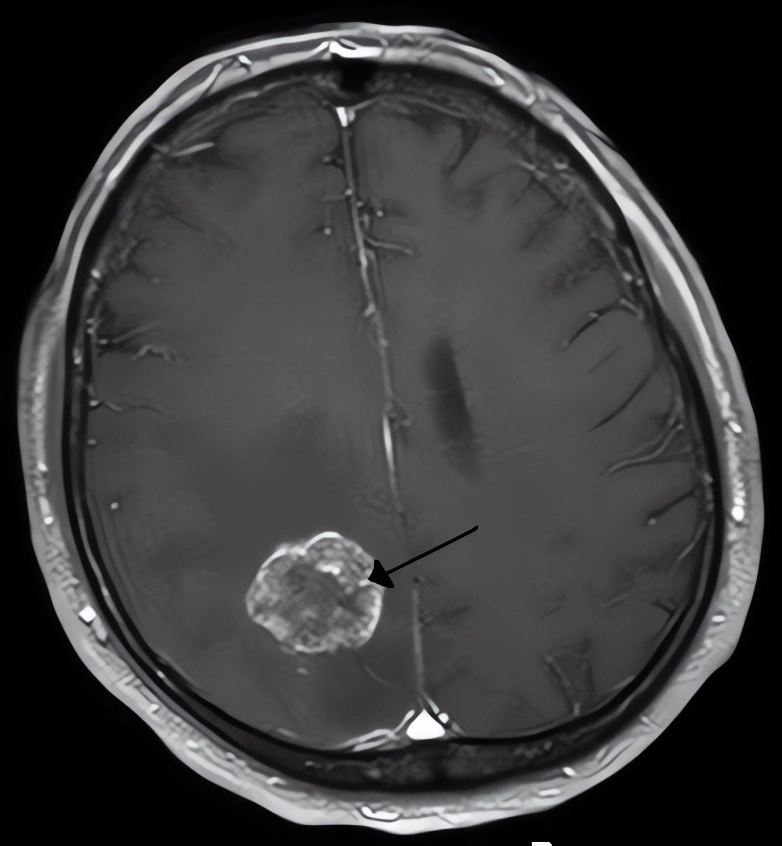

Imaging of a brain tumor.Distributed under CC BY-SA 2.0 DE, from Wiki, without modification.

Glioblastoma (GBM) is the most aggressive and lethal type of primary brain tumor. Despite advances in surgery, radiation, and chemotherapy, the median survival for GBM patients remains poor. The invasive nature of GBM, coupled with its resistance to conventional therapies, necessitates the development of novel therapeutic strategies. Oncolytic virotherapy represents a promising approach that utilizes genetically engineered viruses to selectively target and destroy cancer cells, offering a new avenue for treating this devastating disease.